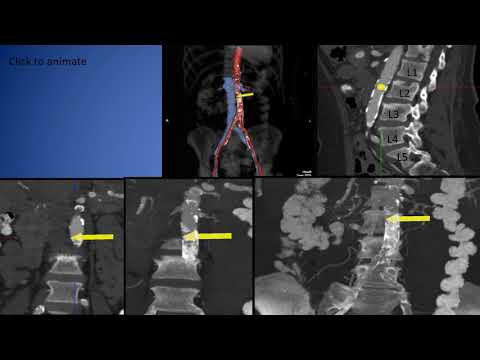

Transcaval TAVR from EPIC-SEC Live 2018

The Transcaval Approach to TAVR - Adam Greenbaum, MD

Transcaval TAVR: Special Technique

Greenbaum Transcaval A Case Example SCAI 2015 San Diego

Transcaval TAVI Case